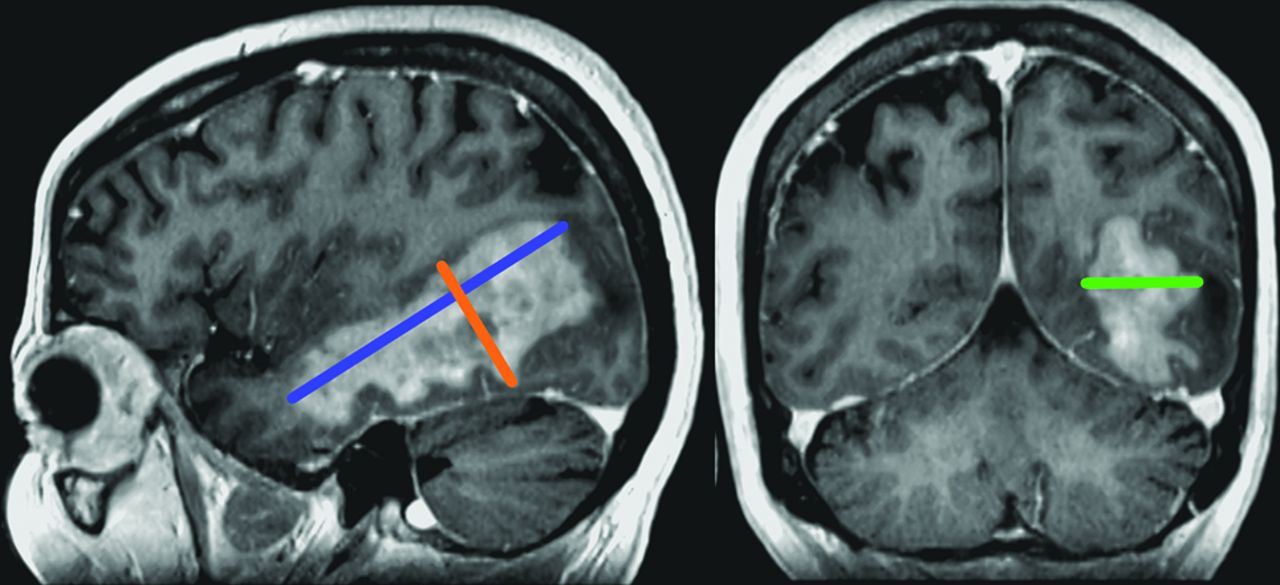

Postcontrast 3D T1 MPRAGE in a 56-year-old woman treated for a left temporal PCNSL. Comparison of the 3D measurements performed by the 2 readers (reader 1, A and B; reader 2, C and D).

Both intra- and interobserver ICCs for 3D, 2D, and longest 1D measurements showed very strong correlations (Table 2). The intraobserver ICC varied from 0.993 to 0.997 in raw units and was calculated to be 0.997 after root manipulation for 2D and 3D measurements. The interobserver ICC varied from 0.967 to 0.992 in raw units and from 0.966 to 0.968 after root manipulation for 2D and 3D, respectively.